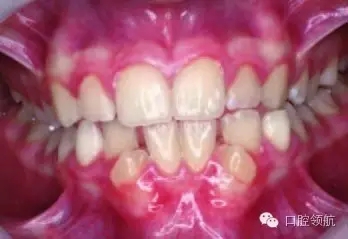

圖2.9中明顯的牙列異常有哪些?

雙側(cè)下頜側(cè)切牙和尖牙移位。

圖2.9

這種異常如何分級(jí)?

牙移位根據(jù)發(fā)生部位、牙齒類型和位置分級(jí)。這種雙側(cè)的移位分級(jí)為Mn.C.I2.